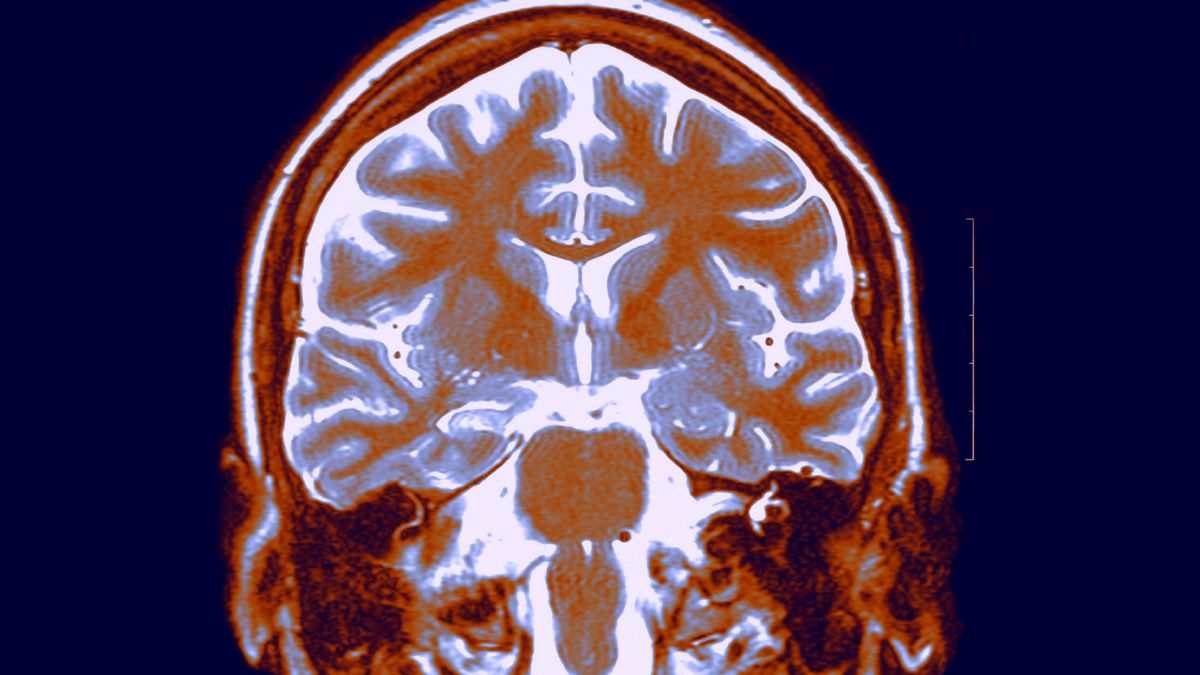

Selon une étude, les fluctuations quotidiennes des hormones dans le corps masculin pourraient jouer un rôle dans le rétrécissement du cerveau au cours de la journée. Après avoir perdu du volume entre le matin et le soir, le cerveau se réinitialise pendant la nuit, recommençant le cycle, comme le montre la recherche.

L’étude a consisté à scanner le cerveau d’un jeune homme de 26 ans 40 fois en 30 jours. Chaque imagerie par résonance magnétique (IRM) a été réalisée à 7 heures ou 20 heures, soit à des moments où les niveaux d’hormones stéroïdes, à savoir la testostérone, le cortisol et l’estradiol, sont respectivement à leur maximum et à leur minimum.

La nouvelle étude a révélé que, tout au long de la journée, le volume cérébral global du sujet diminuait, tout comme l’épaisseur du cortex, la couche externe du cerveau. Le volume de matière grise, qui contient les corps cellulaires des neurones et les connexions entre eux, diminuait en moyenne d’environ 0,6 %.

Deux régions du cortex, appelées cortex occipital et pariétal, ont connu la plus forte contraction. Des changements ont également été observés dans des structures cérébrales plus profondes, notamment le cervelet, le tronc cérébral et certaines parties du cerveau. hippocampeCes parties du cerveau sont respectivement impliquées dans la coordination des mouvements, la transmission d’informations entre le cerveau et le corps et stocker des souvenirs.

La diminution du volume cérébral est parallèle à la diminution quotidienne des hormones. Cependant, on ne sait pas encore si les hormones sont à l’origine des changements cérébraux, ont écrit les auteurs de l’étude dans un rapport publié mercredi (18 septembre) dans Journal des neurosciences.